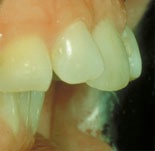

Trångställt bett

Före behandling av trångstätt bett Efter behandling av trångställt bett

Ett trångställt bett med för smal käke, i vy mot gommen. Således en kombination av en malocklusion och en utrymmesanomali. Om man behandlar liknande anomalier i rätt tid under ungdomsåren kan man till och med, som här, bredda käken med hjälp av tandreglering. Barnets egen växt hjälper till.